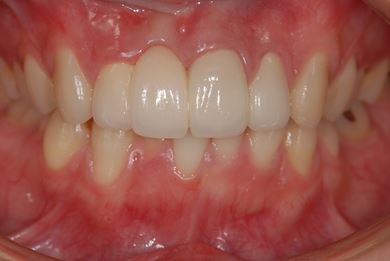

セラミックの症例写真 SHINBI

セラミック治療

| 性別/年齢 | 女性 / 20歳 | ||||||||||||||||||||||||||||||||

| 主訴 | 神経が死んで来ている歯が痛むので、治療をして欲しい。歯並びも良くできるのであればして欲しい。 | ||||||||||||||||||||||||||||||||

| 治療方針 | ジルコニアオールセラミック(クラウン1本、ブリッジ3本)、セラミック用土台2本 | ||||||||||||||||||||||||||||||||

| 総治療費 | 773,850円 | ||||||||||||||||||||||||||||||||

| 治療期間 | 5ヶ月 |